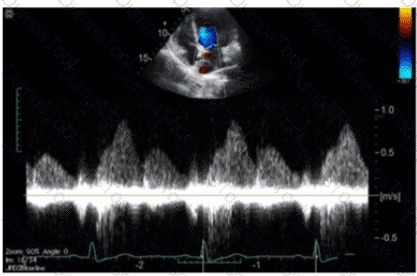

The sonographer obtains this Doppler signal while using the non-imaging transducer in the apical position. What is the best way to differentiate between mitral regurgitation and aortic stenosis signals in the waveform shown in this image?